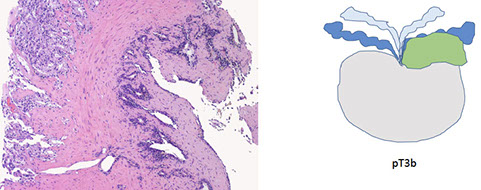

EXTRAPROSTATIC EXTENSION (EPE)

Tumor beyond confines of gland

• Admixed with periprostatic adipose tissue; easily recognized in posterolateral, posterior, lateral regions

• Tumor in skeletal muscle does NOT constitute EPE

• Extent ( nonfocal ) and location of EPE tshould be documented

SEMINAL VESICLE INVASION

Tumor invades muscular wall of extraprostatic portion of seminal vesicles

SURGICAL MARGIN INVOLVEMENT (+SM)

• Tumor extends extraprostatic or intraprostatic) to prostate inked surface

• For +SM document:

- Location

- Extent (limited: <3 or non limited: ≥3 mm; linear length of SM)

- Gleason pattern @ +SM: pattern 3, 4, 5